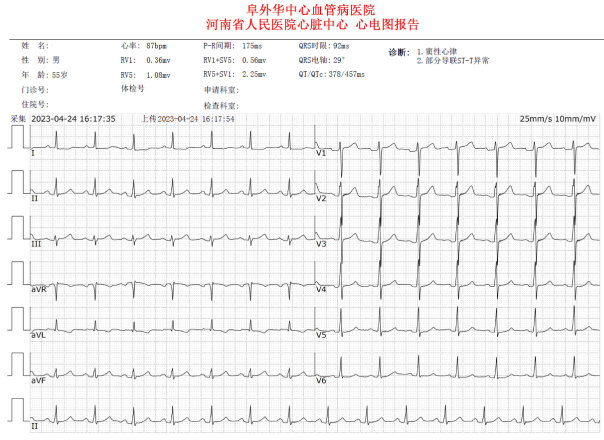

入院后,心电图检查示:窦性心率,部分导联ST-T段异常;心脏超声示:轻度三尖瓣反流,左室舒张功能减低,EF 59%(组图2)。

组图2:心电图及心脏超声检查